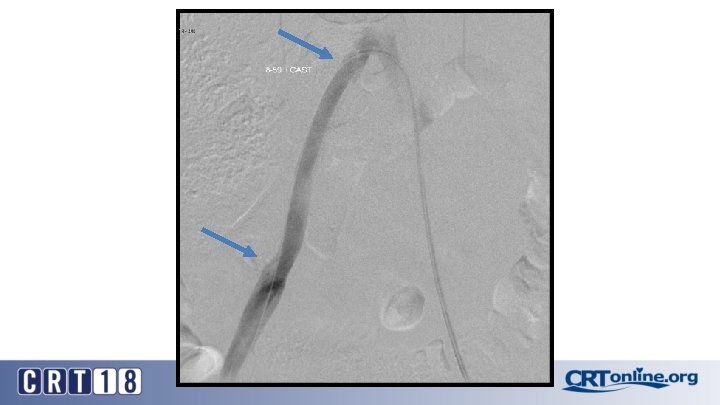

CS Compared to BMS in iliac occlusion • 2009 and December 2015, 128 iliac artery occlusions were stented • A CS was implanted in 78 iliac arteries (61%) and a BMS in 50 (49%) • After propensity score matching (lesion site and length separated and associated femoropopliteal disease included) (47 for each group). • Technical success was 98% • Complication rates same: 12% vs. 12%, p = 1. 0 • 30 day mortality rates same: 2% vs. 2%, p = 1. 0 Piazza M, et al. Outcomes of polytetrafluoroethylene-covered stent versus bare-metal stent in the primary treatment of severe iliac artery obstructive lesions. J Vasc Surg. 2015; 62(5): 1210 -8.

CS superior to BMS, in the right setting • At 36 months (average 23 ± 17) overall primary patency only approached significance: 87% vs. 66%, p =. 06 • For TASC D, CS: 88% vs. BMS: 54% (p =. 03) • Patency was in favor of CSs for occlusions > 3. 5 cm in length (p =. 04), total lesion length > 6 cm (p =. 04), and occlusion with calcification > 75% of the arterial wall circumference (p =. 01) • Kissing stent patency also superior with CS